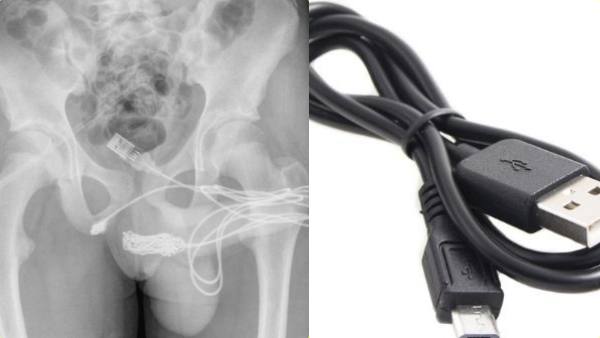

ஆணுறுப்பின் நீளத்தை அளக்க யூஎஸ்பி கேபிளை பிறப்புறுப்பில் நுழைத்த சிறுவன்.. கடைசியில் நடந்தது என்ன?

லண்டன்: லண்டனில் ஆணுறுப்பு எத்தனை நீளமாக இருக்கிறது என்பதை தெரிந்து கொள்ள தனது பிறப்புறுப்பில் யூஎஸ்பி கேபிளை நுழைத்த போது அது சிக்கிக் கொண்ட சம்பவம் அதிர்ச்சியை ஏற்படுத்தியுள்ளது.

போனுக்கு சார்ஜ் போடும் யூஎஸ்பி கேபிளை உள்ளே நுழைக்கலாம். அது எவ்வளவு தூரம் போகிறது என பார்க்கலாம். ஒரு கட்டத்திற்கு மேல் கேபிள் உள்ளே நுழையாவிட்டால், அந்த இடத்தை மார்க் செய்துக் கொண்டு கேபிளை உள்ளிருந்து இழுத்து விடலாம்.

அப்போது உலோக கம்பியை கொண்டு கேபிளை அகற்ற மருத்துவர்கள் முயற்சிததனர். ஆனால் அது கடினமான வேலையாக இருந்தது. இதனால் அறுவை சிகிச்சை செய்ய வேண்டிய நிலை ஏற்பட்டது. அறுவை சிகிச்சை மூலமே அந்த கேபிள் வெளியே எடுக்கப்பட்டது.

அப்போதுதான் அந்த கேபிள் சிறுவனின் ஆண் குறிக்குள் 70 செ.மீ. அளவு உள்ளே இருந்தது. இதையடுத்து மருத்துவர்களின் கண்காணிப்பில் 24 மணி நேரம் வைக்கப்பட்டிருந்த சிறுவன் டிஸ்சார்ஜ் செய்யப்பட்டான். விளையாட்டு வினையாகும் என்பதற்கு இது சிறந்த உதாரணம்.